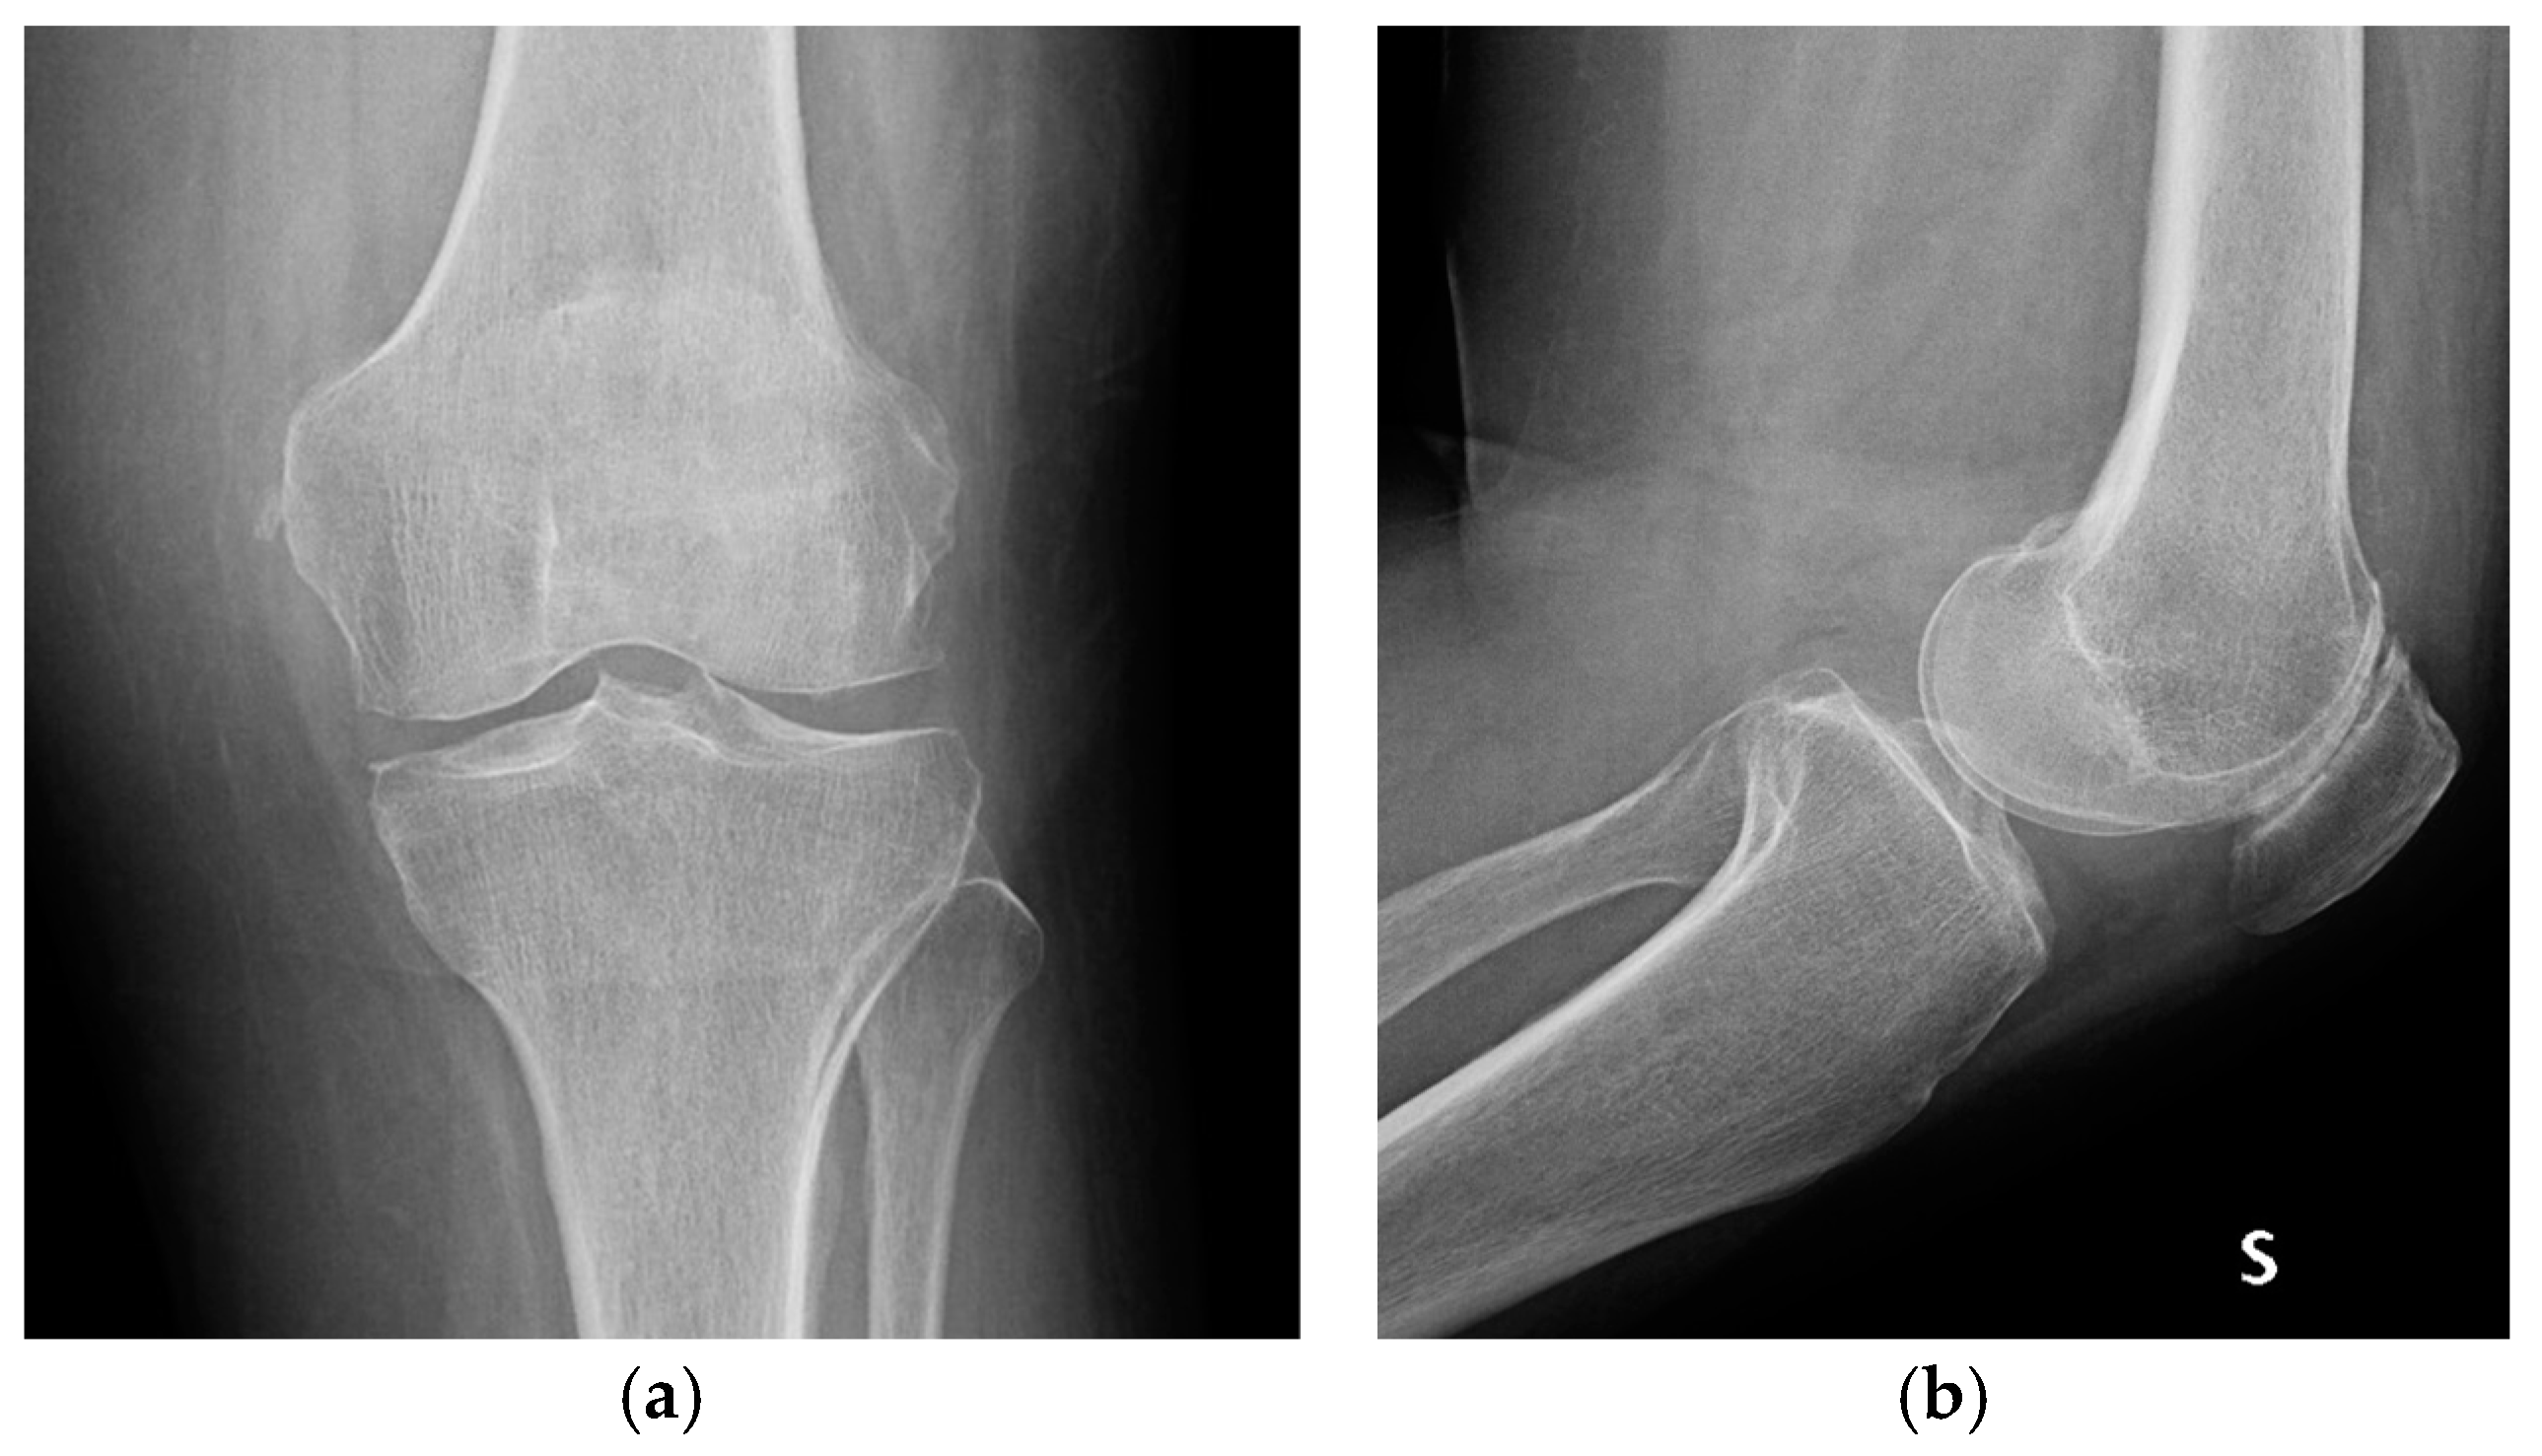

| Stage I | Opacity of fluid, redness of the synovial membrane, possible petechial bleeding, no radiological alterations |

| Stage II | Severe inflammation, fibrinous deposition, pus, no radiological alterations |

| Stage III | Thickening of the synovial membrane, compartment formation (“sponge-like” arthroscopic view, especially in the suprapatellar pouch), no radiological alterations |

| Stage IV | Aggressive pannus with infiltration of the cartilage, possibly undermining the cartilage, radiological signs of subchondral osteolysis, possible osseous erosions and cysts |